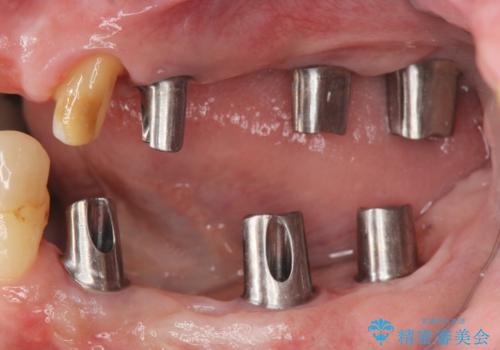

多発した虫歯による咬合崩壊 インプラントを用いた全顎治療

歯の破折・再発した大きな虫歯・根尖病変・歯の欠損、これらの問題を根管治療・歯周外科・インプラント治療・セラミック補綴を行うことで一つづつ解決し安定した咬合状となるよう治療を進めます。

口腔内全体を治療する全顎治療は、期間も長く外科を行う回数も多いためしっかりと通っていただくことが必要不可欠になります。